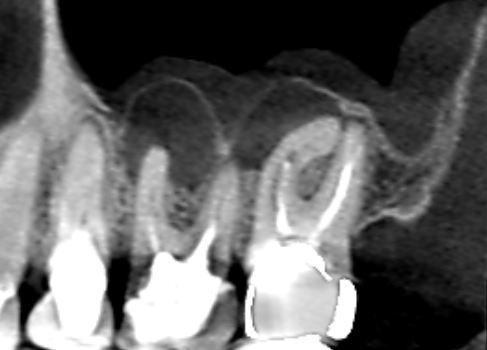

続きを読むVol.16 歯の神経は生きているのに根尖病変様の歯槽骨吸収があったケース

- むし歯治療・ パーフォレーションリペア・ 根尖病変・ 歯科症例・ 精密根管治療

上顎の奥歯の歯茎が腫れ、できるだけ自分の歯を残したいということで来院された患者さんです。初診時のCT…